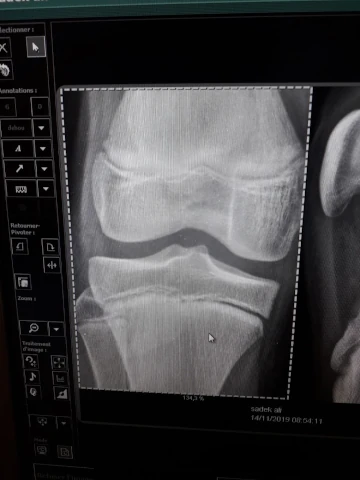

Arthrose

img